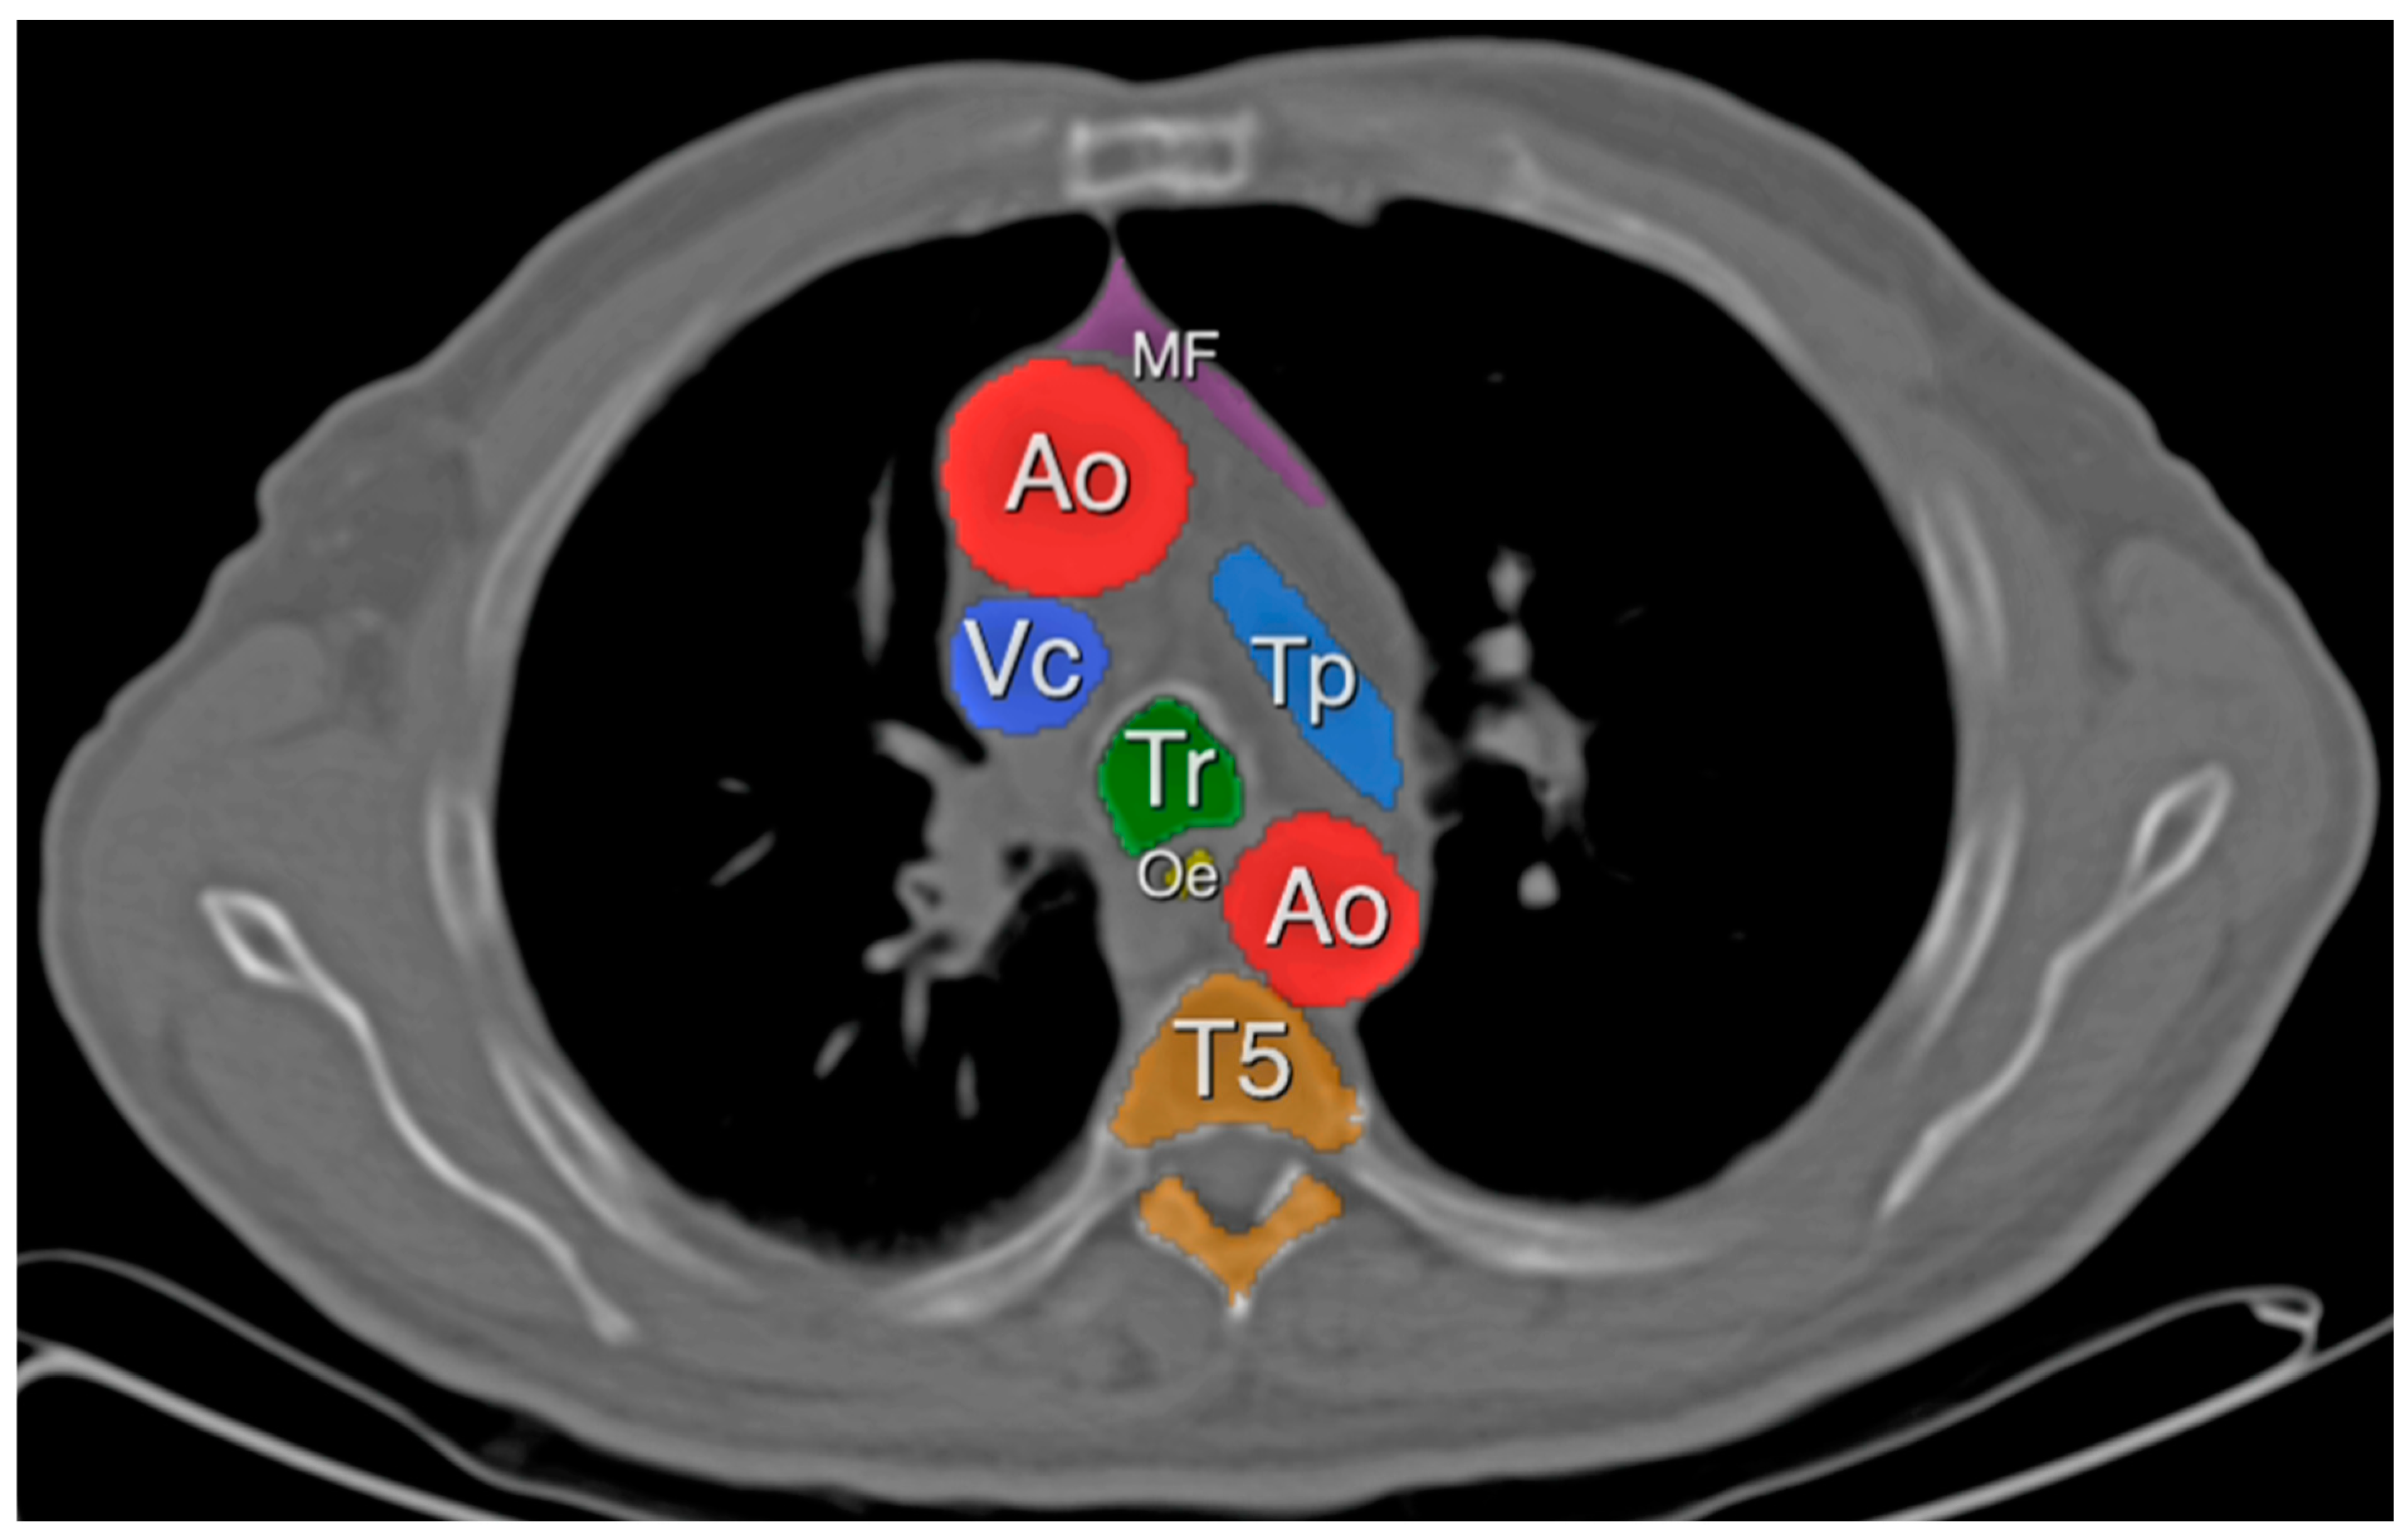

2.3. Definitions

3.2. Mediastinal Adipose Tissue